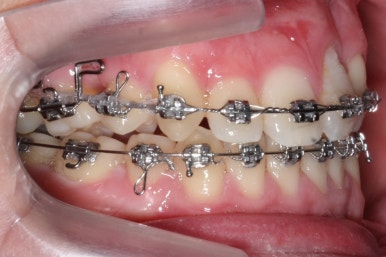

가장 최근의 사진입니다.

아직 치료 종료는 안되었으나 약간의 조절을 더하면 치료를 마무리할 수 있을 것 같습니다.

물론 윗니 한 쪽은 작은 앞니가 없고 한 쪽은 작은 어금니가 없기 때문에 중앙선이 100% 일치하지는 못하겠지만 기능적으로나 미적으로나 매우 개선되었음은 틀림없습니다.